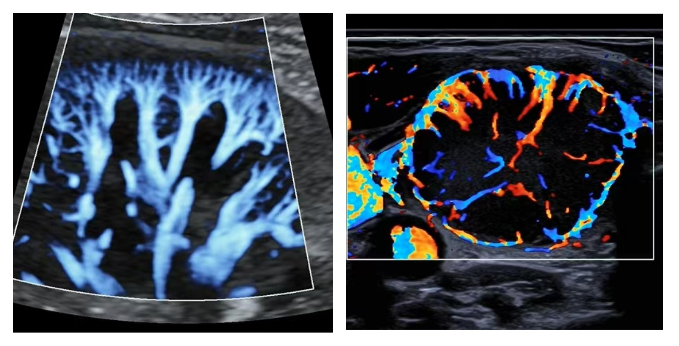

此次引入的高端设备集成了多项前沿超声成像技术,具备显著的技术优势:

新一代智能成像平台搭载超高清智能成像系统,图像分辨率较旧设备有显著提升,能够清晰显示毫米级微小病灶。如迈瑞ResonaA20T高频探头可清晰呈现神经、肌腱等细微结构,为疼痛治疗、运动损伤提供精准的诊断信息。

“微血流”检测技术能够捕捉极低速血流信号,显著增强肿瘤良恶性的鉴别能力。